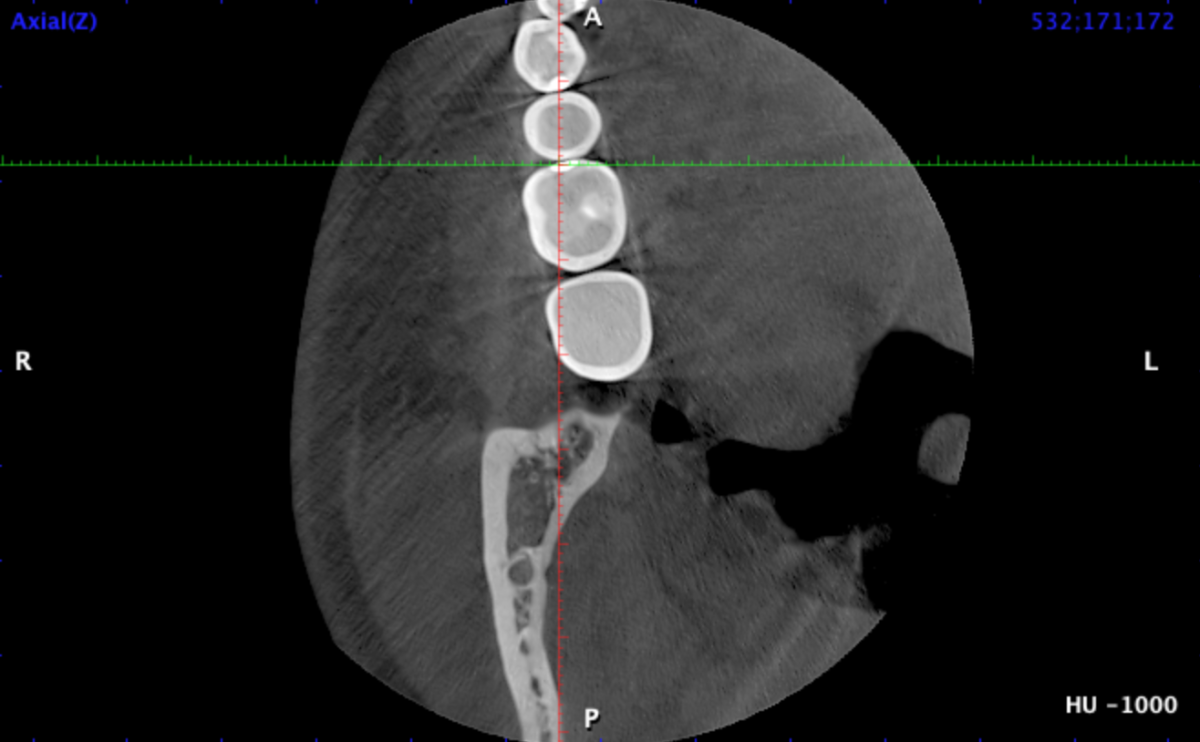

Я сделал клкт сектора 4-5-6-7 зубов справа снизу, могу приложить, если нужно. Я проходил ортодонтическое лечение, после которого у меня случилась рецессия десны на передних нижних зубах, вплоть до клыков. На самом оголоенном участке 1-2 была пластика десны пару лет назад, стало лучше. Удалены все 4 зуба мудрости